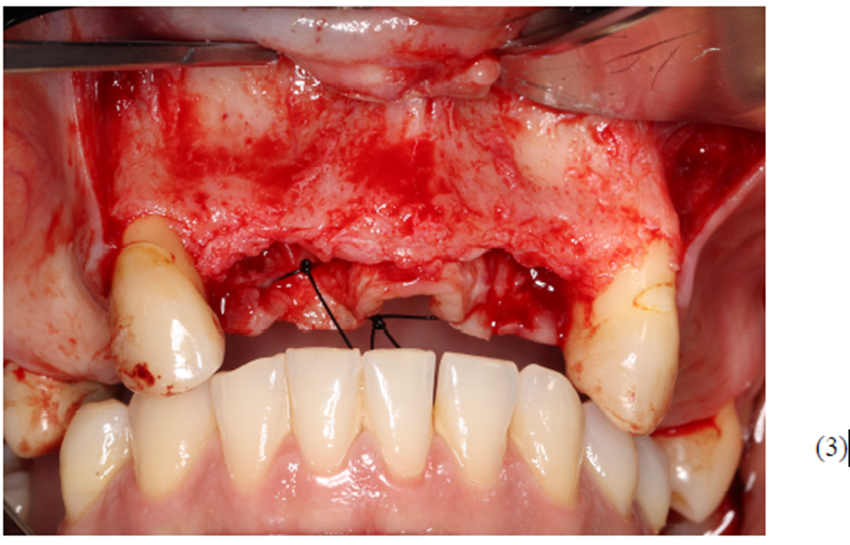

Figuras 3,4,5,6,7 e 8 – Sequência do primeiro ato cirúrgico, onde podemos observar (Figura 3) a incisão do tipo Newmann modificada para ampla visualização do campo operatório e as extrações dentárias. Podemos observar também a descorticalização do processo alveolar e a instalação dos parafusos tipo tenda Implacil De Bortoli de 10 mm, respeitando a distância de pelo menos 3 mm entre cabeças (Figura 4).